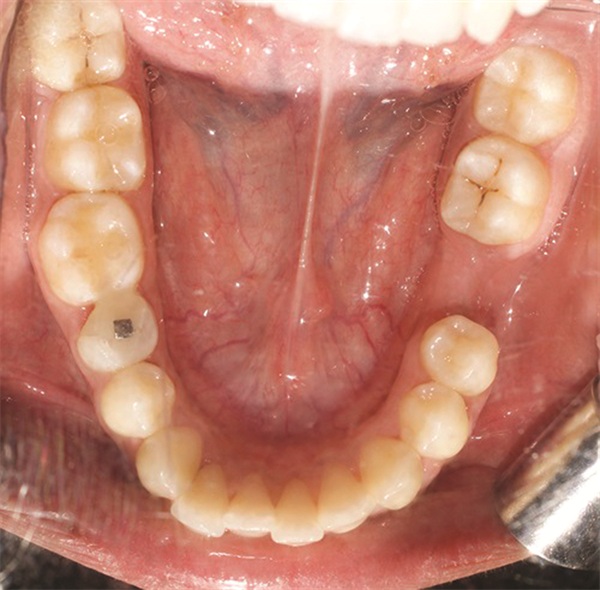

The diagnostic findings told a more complicated story. The patient presented with a skeletal Class II relationship, bilateral Class I molar and canine relationships, collapsed arches, and proclined incisors in both arches. Both midlines were shifted to the right. She also exhibited crossbite of the upper right first molar and upper right lateral incisor, a discrepancy between centric relation and centric occlusion, and a noticeable cant in the lower anterior segment. Her dental history included previous extractions of the upper right third molar and upper left second molar (Figs. 1–12).

Fig. 3